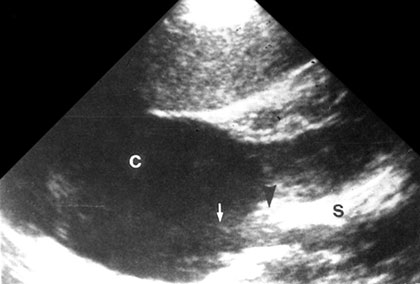

Hence echoes within the returning beam include from liquid as well as solid structure and averaged by the process or consequently the boundaries between solid tissues and fluid is seen as a low echogenic and indistinct structure. It can mimic sludge or layered material (concrements, blood clots) in the urinary bladder (Figs 1.19 and 1.20).

Fig. 1.20: Beam width artifact: A weaker beam spread artifact misplaces echoes from the more reflective sinus tissues (arrow-head) into in renal cyst (arrow)